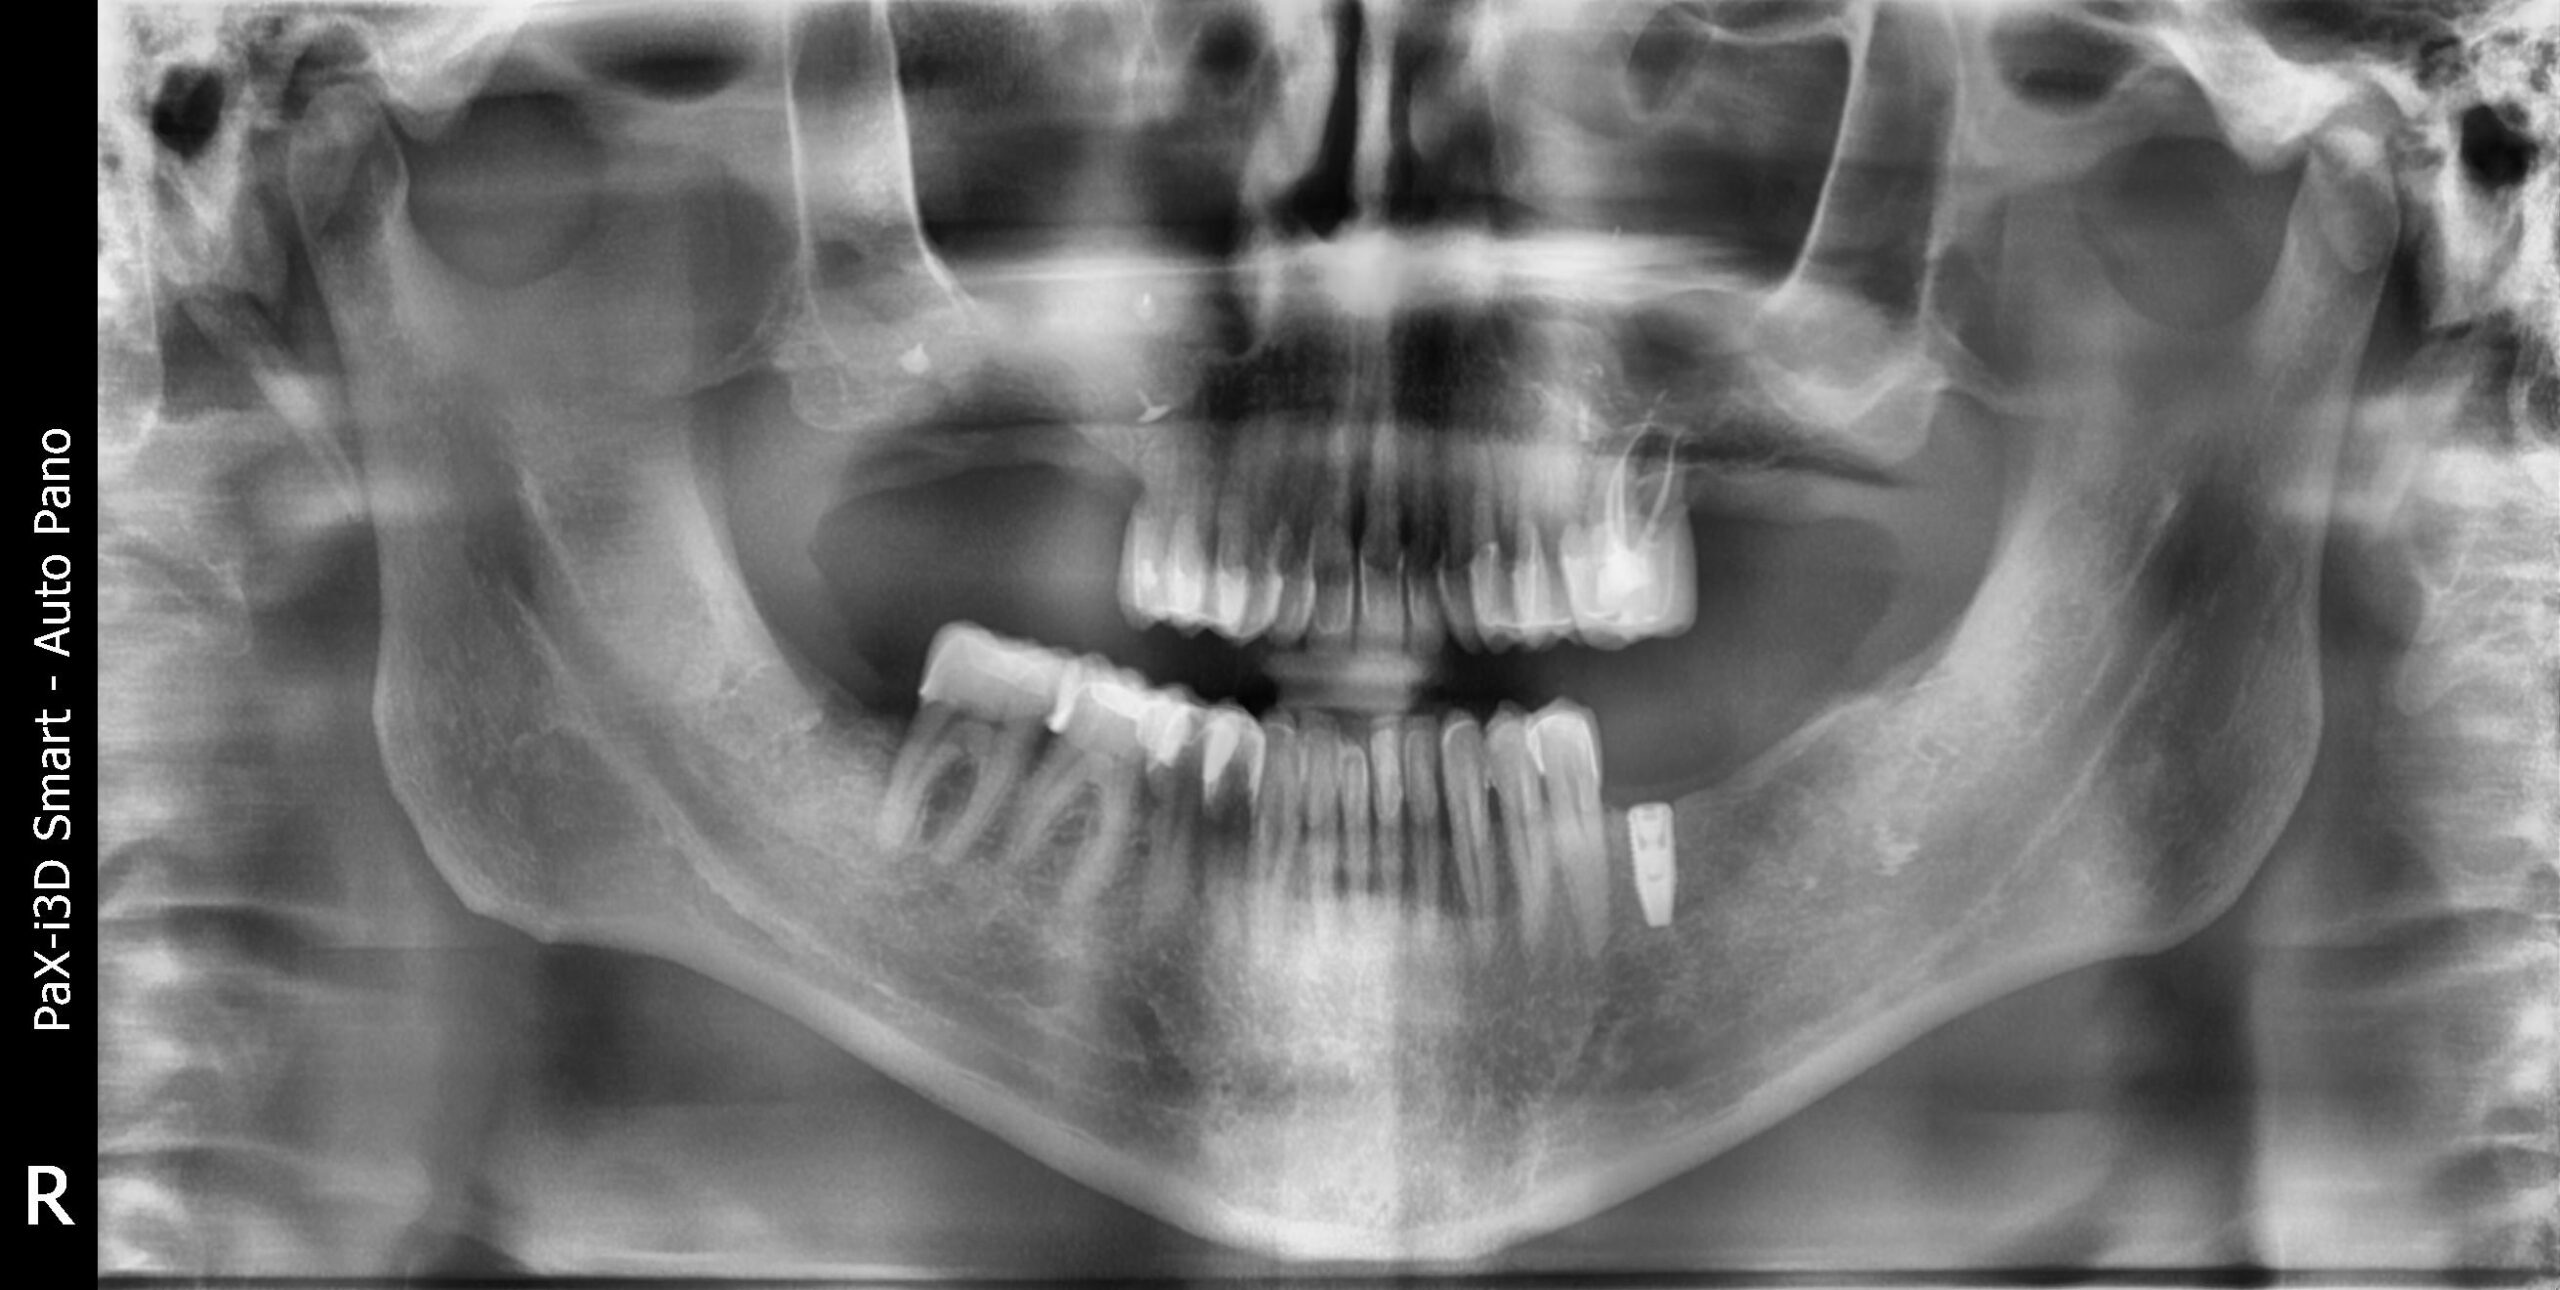

1. Pérdida ósea en el sector posterior

2. Enfermedad periodontal con retracción gingival

3. Mordida cruzada posterior

4. Ausencia de varias piezas dentales